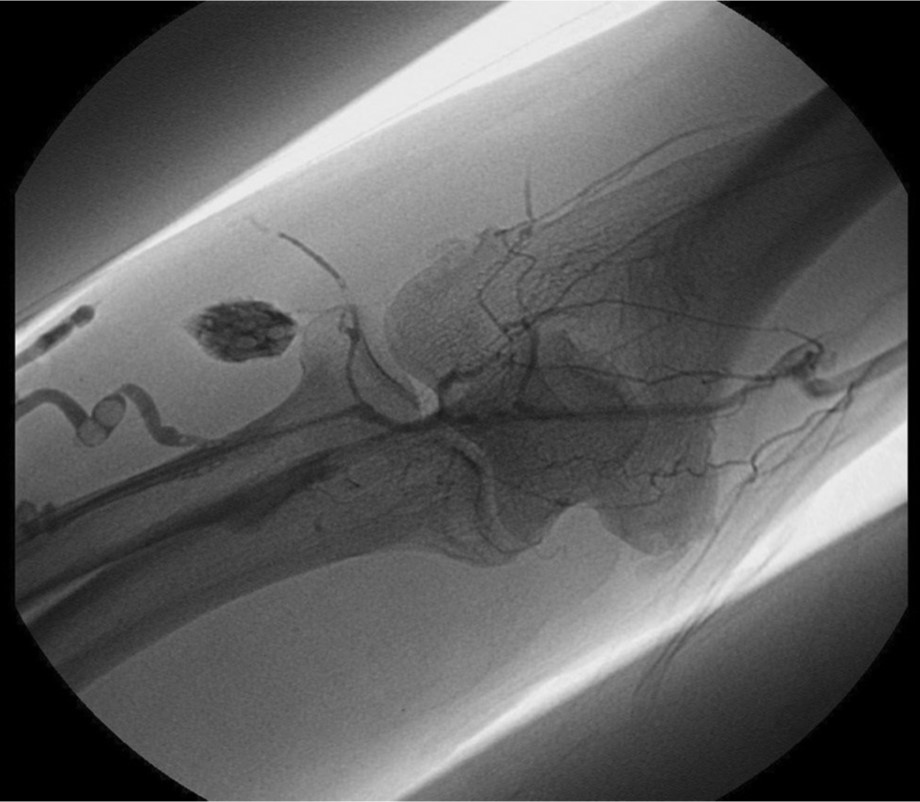

Initial shuntogram 상 total stenotic occlusion된 antecubital vein과 cephalic & basilic veins이 확인되었다(Fig. 1) 투시하에서 더 이상의 outflow vein을 확인할 수 없었으며 초음파상 1mm 크기에 가까운 흔적으로 확인되었다(Fig. 2). 7Fr, 24cm sheath(Accu-Sheath, Sung wonmedical, Korea, Cheongju) 로 폐색된 앞부위까지 전진시킨 후, 투시를 보조수단으로 하며 초음파를 main 유도 기구로 사용하여 real time으로 초음파 probe를 0.035’ J-tip & straight-tip guide wires(Terumo, Tokyo, Japan)와 5 Fr Kumpe catheter(Soft-Vu, AngioDynamics, USA, NY) 바로 위에 위치 시키면서 wire를 전진시켰다(Fig. 3). 시술 중 guide wire 가 혈관 외부로 뚫고 나가며 parenchymal injury를 유발하였다(Fig. 4A, B). 그 후 venous true lumen을 찾 angioplasty를 시행하였다(Fig. 5). 마지막 shuntogram 상 더 이상의 혈관 손상이 없이 재개통된 것을 확인하고 시술을 종료하였다(Fig. 6).

Fig. 5.

Guide wire negotiation to true venous lumen and balloon angioplasty at antecuvital and basilica vein

Fig. 6.

Final shuntogram : relatively good out flow in AV fistula